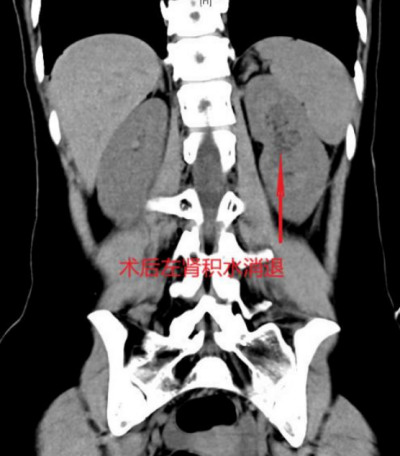

得益于微创手术创伤小、疼痛轻的优势,结合加速康复外科理念,张柔术后恢复顺利。手术当天即可下床活动,次日经评估拔除引流管,复查显示其左肾积水显著消退,肾功能逐步恢复,腰部不适基本消失。张柔精神状态良好,最终如期参加面试并成功获得心仪职位。